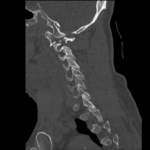

Unstable cervical spine (c-spine) fractures are of high concern in traumatic incidents because they may result in significant morbidity and mortality. This is a case of a 44-year-old male who presents to the Emergency Department (ED) with neck pain after recreational wrestling and was found to have an unstable C-spine fracture. His treatment course was complicated by multiple interrupted hospital stays due to leaving against medical advice (AMA) and subsequent returns to the emergency department. The patient received both CT and MRI imaging and ultimately underwent occiput to C3 fusion with drain placement with a favorable outcome. This case report highlights the diagnosis and treatment of a patient with an unstable c- spine fracture. Key lessons from the case include the importance of timely recognition of patients with a potential c-spine fracture and identifying those who are at risk for nonadherence to medical treatment plans in order to provide interventions and improve chances of adherence. For patients in which pre-hospital care is involved, such as emergency medical services (EMS), recognition and appropriate care, such as c-spine stabilization, may be important for long-term outcomes.